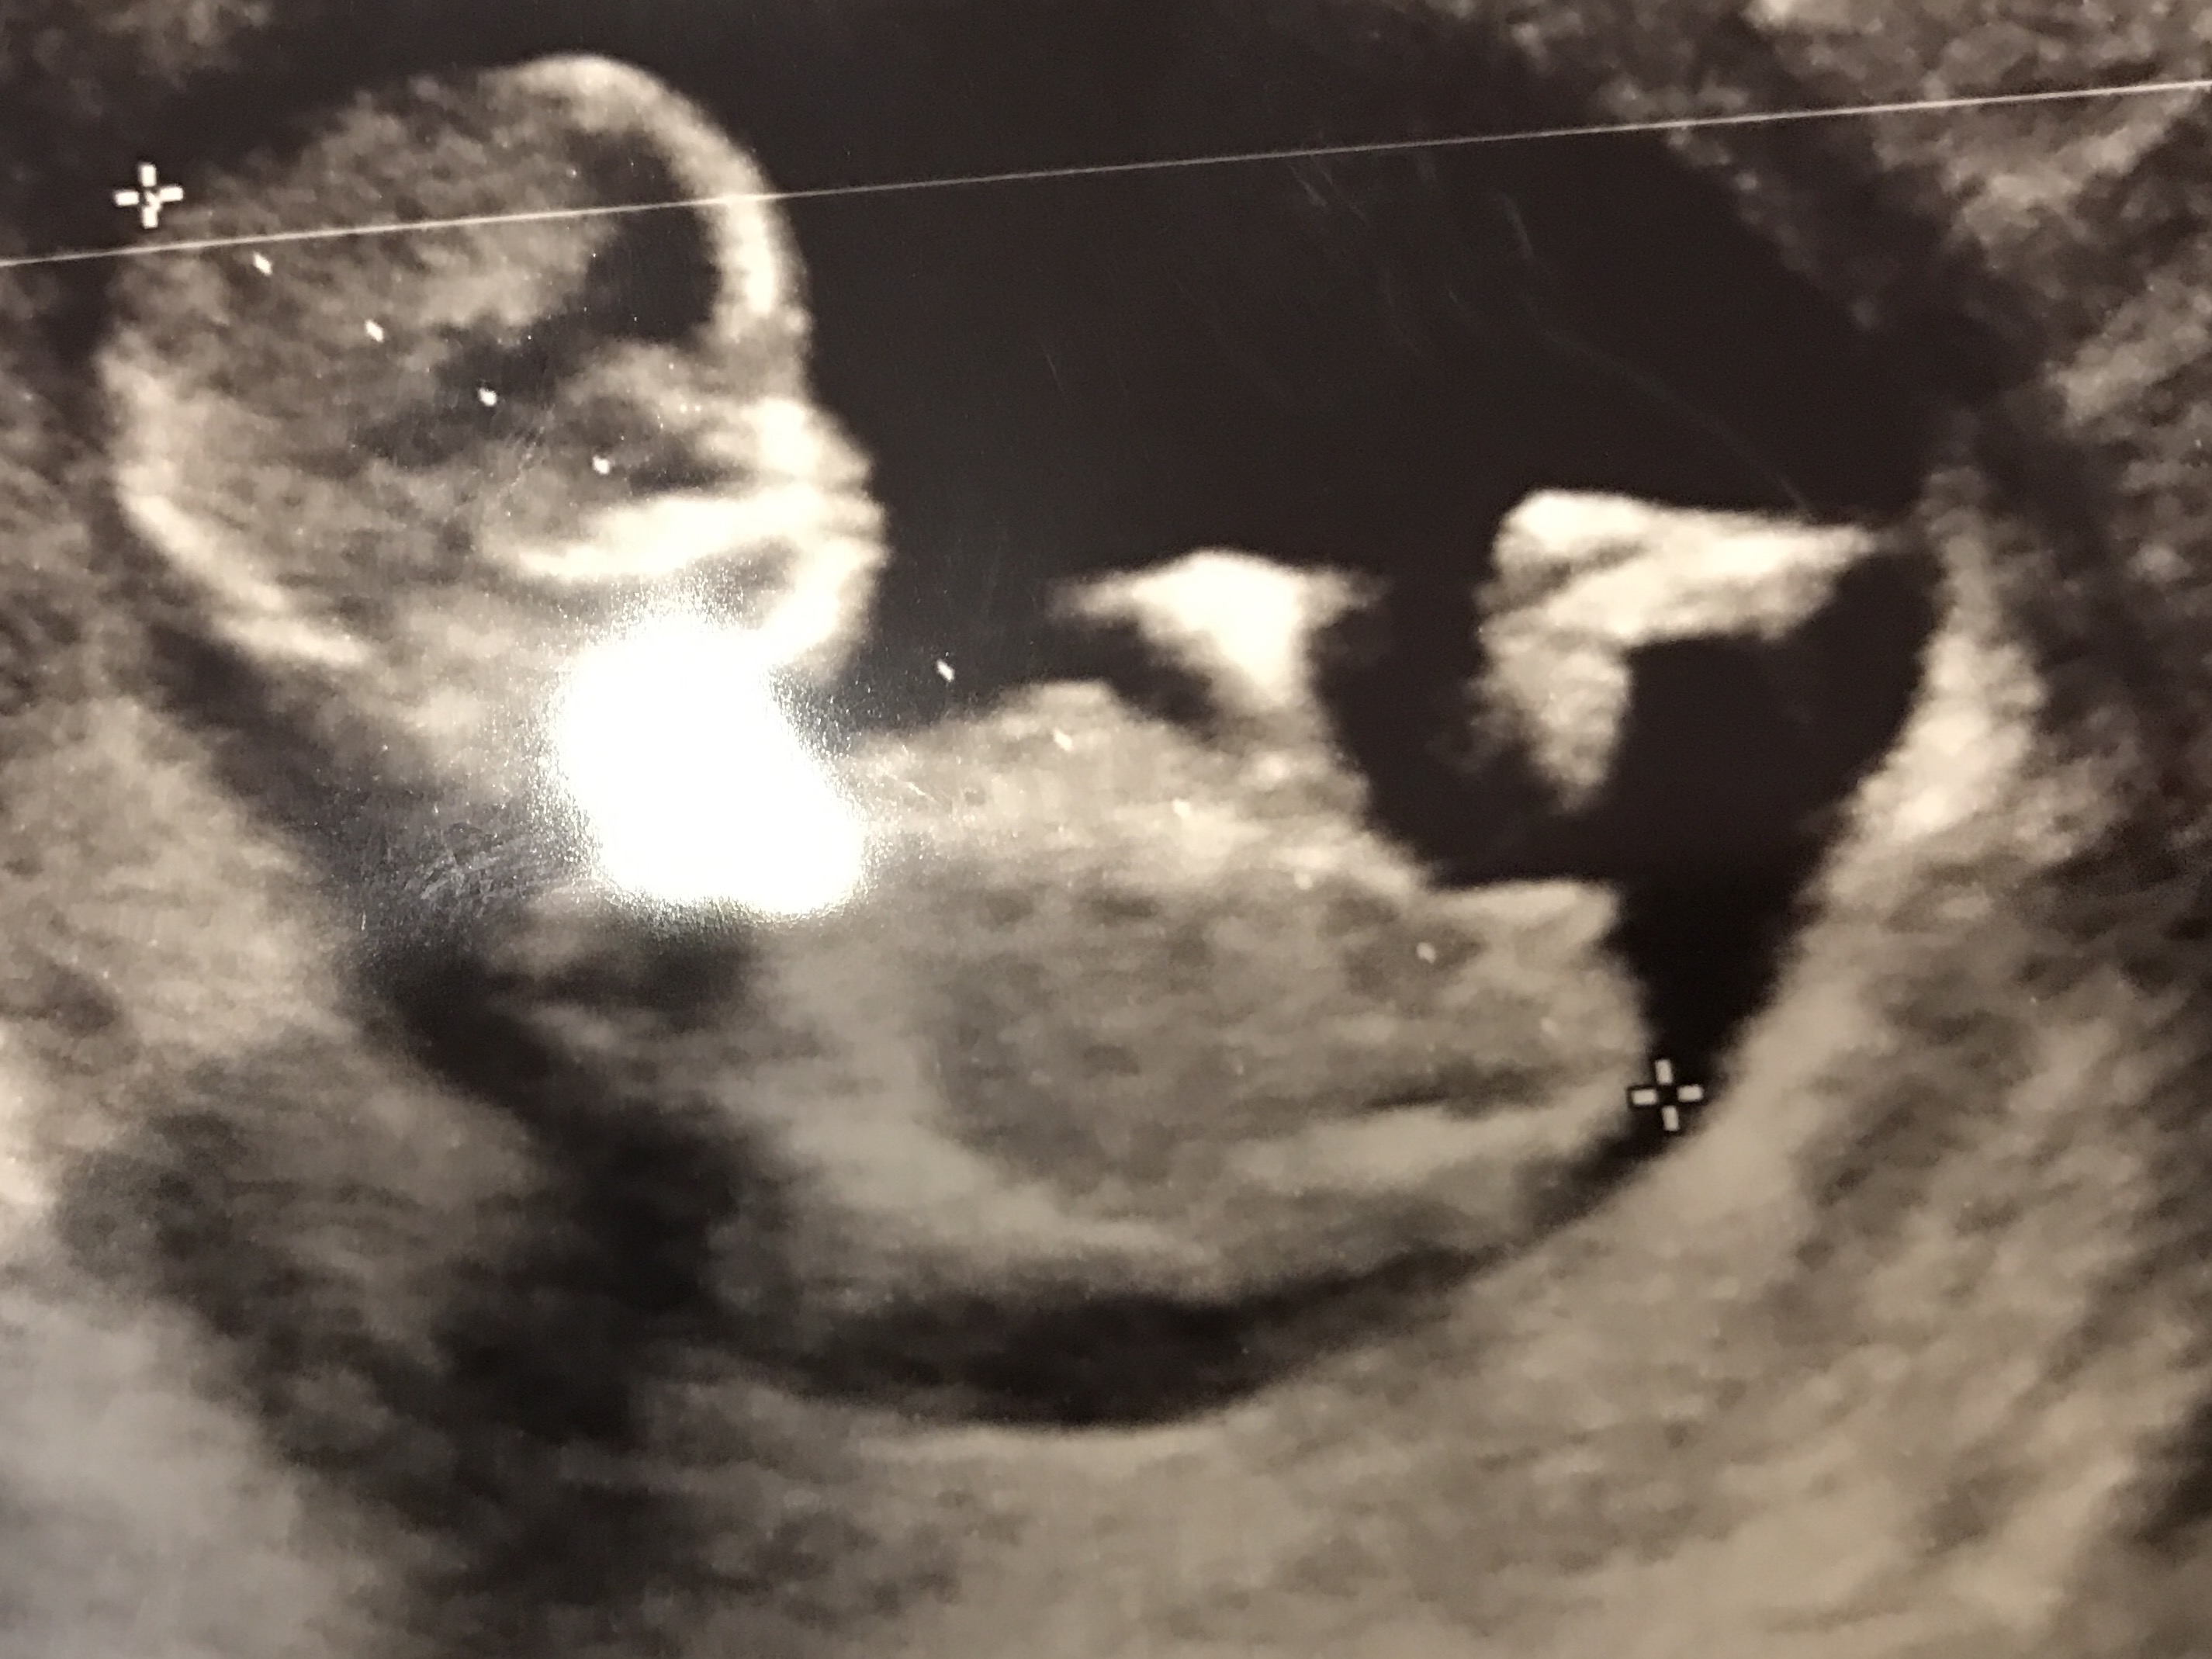

13 weeks 4 days

Maybe boy? The nub is short and looks curved up at the end.

this is kind of a weird pic for me, do you have any other ones? The baby is sooo curled up.

It's the only image I have with the nub